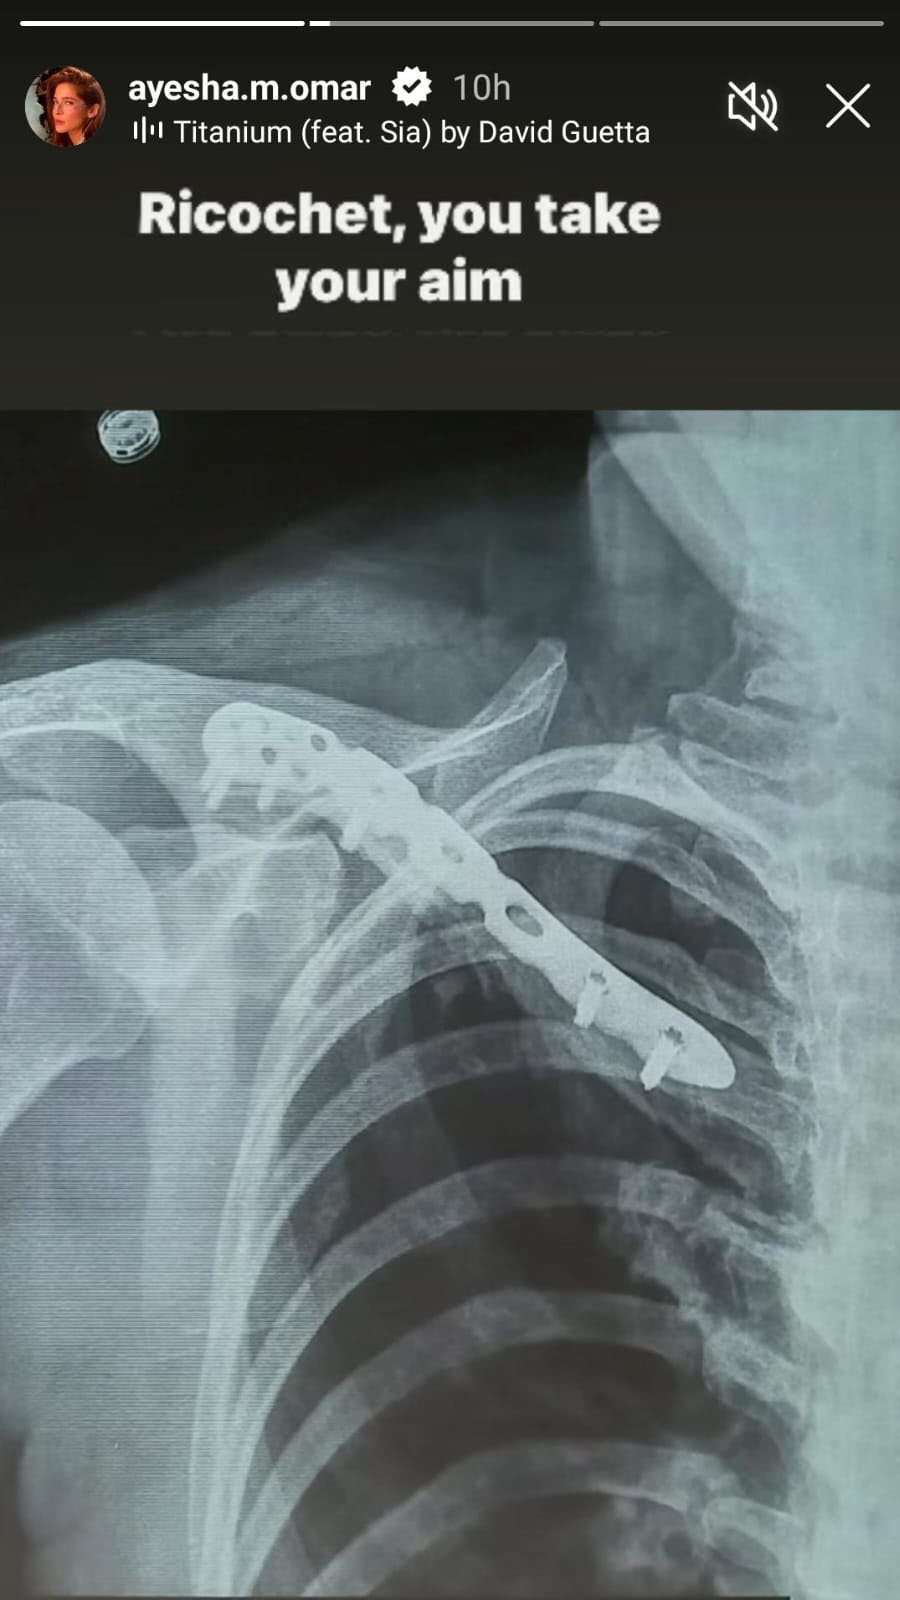

اب عائشہ عُمر نے اپنے آفیشل انسٹاگرام کی اسٹوری میں اپنی ‘کالر بون’ سرجری کی تصویر شیئر کی ہے جس میں اداکارہ کی گردن سے کندھے تک ہونے والی سرجری دیکھی جاسکتی ہے۔اس کے علاوہ عائشہ عُمر نے اپنی ‘کالر بون’ کے ایکسرے کی تصویر بھی اپنے مداحوں کے ساتھ انسٹاگرام اسٹوری میں شیئر کی۔